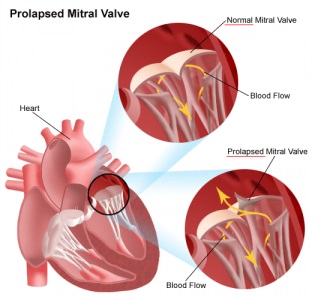

Nézzük meg a Google-ban az eredeti kép nyelvén kérésre "mitralis szelep prolapsus".

Több kép normát és prolapsust tartalmaz. A kép nagyítása egérkattintással. Piros aláhúzta a szelepek szimbólumát és a prolapszust, a sárga nyilak a vér áramlását mutatják a szisztolába:

Néhány világosabban értelmezett illusztráció.